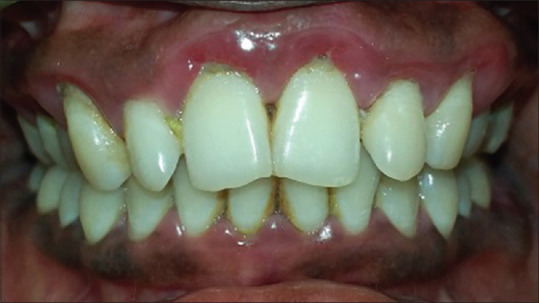

Materials and methods: A study included 100 subjects divided into four groups. Group I: stable coronary artery disease with chronic periodontitis, Group II: stable coronary artery disease without chronic periodontitis, Group III: chronic periodontitis without coronary artery disease, and Group IV: healthy controls. Gingival index, Russell's periodontal index, pocket depth, and clinical attachment level were recorded. Venous blood was collected from the patients, and serum fibrinogen, CRP, and lipid profile levels were estimated.